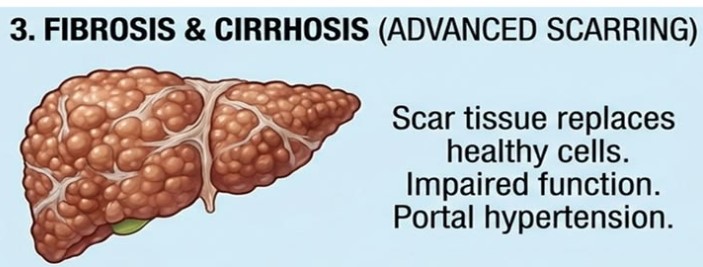

يُعد تليف الكبد من الأمراض المزمنة التي تتطور تدريجيًا نتيجة تلف خلايا الكبد السليمة واستبدالها بنسيج ندبي يضعف وظائفه الحيوية بشكل واضح. ومع مرور الوقت، يفقد الكبد قدرته على تنقية الدم وتنظيم العمليات الحيوية داخل الجسم بكفاءة طبيعية. وتكمن خطورته في أنه يتطور بصمت في مراحله الأولى قبل أن تظهر مضاعفاته بشكل واضح على صحة المريض.

تليّف الكبد هو حالة مرضية مزمنة تحدث عندما تتعرض أنسجة الكبد السليمة لضرر متكرر يؤدي إلى تكوّن نسيج ندبي بدلًا من الخلايا الطبيعية، مما يضعف قدرة الكبد على أداء وظائفه الحيوية بكفاءة. ومع تطور الحالة، يفقد الكبد تدريجيًا مرونته ووظائفه الأساسية، وقد يتفاقم الأمر ليصل إلى مضاعفات خطيرة مثل تشرّب الكبد (التشمع)، أو فشل وظائف الكبد، أو ارتفاع ضغط الدم في الوريد البابي.

يبدأ تليّف الكبد كردّ فعل دفاعي طبيعي من الجسم عند تعرض أنسجة الكبد للالتهاب أو الإصابة المتكررة نتيجة العوامل المسببة للمرض. في هذه المرحلة، يتم تنشيط آليات الالتئام داخل الكبد، حيث يزداد إنتاج بروتينات مثل الكولاجين بهدف إصلاح الأنسجة المتضررة.

ومع استمرار التحفيز الالتهابي وتكرار الإصابة، لا يتم التخلص من هذه البروتينات بشكل طبيعي، بل تتراكم داخل النسيج الكبدي إلى جانب البروتينات السكرية، مما يؤدي تدريجيًا إلى تغيّر بنية الكبد الطبيعية. ومع مرور الوقت، تتحول هذه التراكمات إلى نسيج ندبي صلب يحل محل الخلايا السليمة، وهو ما يُعرف بتليّف الكبد ويؤدي إلى تراجع وظائفه الحيوية بشكل تدريجي.

مرض تليف الكبد

يمثل تليف الكبد المرحلة المبكرة من المرض، والتي تبدأ فيها أنسجة الكبد بالتعرض للتندب نتيجة التعرض المستمر للعوامل المسببة للالتهاب أو التلف. في هذه المرحلة يكون الضرر محدودًا نسبيًا، وقد تظل وظائف الكبد قادرة على الأداء بدرجات متفاوتة. لكن استمرار السبب المؤدي للتليف قد يؤدي تدريجيًا إلى تفاقم الحالة وانتقالها إلى مراحل أكثر شدة.

مرض تشمع الكبد

تشمع الكبد هو المرحلة المتقدمة والنهائية من تليّف الكبد، حيث يغلب النسيج الندبي على معظم أنسجة الكبد، مما يؤدي إلى تشوّه بنيته الطبيعية بشكل واضح وتراجع شديد في قدرته على أداء وظائفه الحيوية. ويُشار إلى هذه المرحلة أيضًا بأنها المرحلة الرابعة من التليّف (F4)، ضمن نظام تصنيف مراحل تليّف الكبد الذي يتدرج من (F0) إلى (F4)، حيث يعكس كل مستوى درجة تطور التندب داخل الكبد.